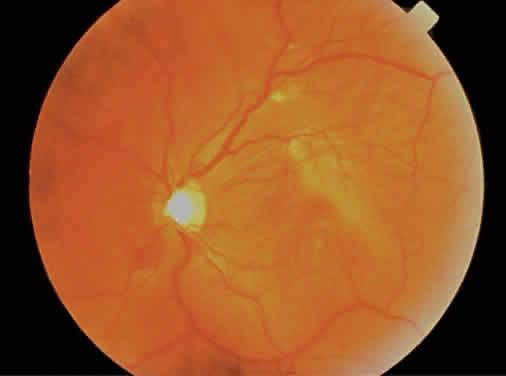

The fundus finding that is most commonly seen with low to moderate degrees of myopia (less than -6 diopters) is a scleral or choroidal crescent located adjacent to the optic nerve head (Fig. 8).26 As the globe expands, the retina, RPE, Bruch's membrane, and choroid are pulled away from the optic nerve head, resulting in the scleral crescent (Fig. 9). In this area, the sclera is clearly visible given the absence of the RPE, Bruch's membrane, and choroid, which are usually found at the temporal aspect of the disc.27,28 In physiologic myopia, its width rarely exceeds one third of a disc diameter. Stenstrom and other investigators29–32 showed that the presence of a peripapillary crescent correlated with increasing axial length but not total refractive power (corneal plus lens power) of the eye.

Fig. 8. Fundus photograph of a pathologically myopic eye. There is diffuse retinal pigment epithelium thinning with increased visualization of the choroidal vasculature, extensive peripapillary atrophy, a lacquer crack extending from the optic disc through the macula, and choroidal neovascularization with subretinal hemorrhage. (Courtesy of Wills Eye Hospital, Philadelphia, PA.)

Fig. 9. Schematic illustration of an eye with myopic degeneration. The choroid, Bruch's membrane, and the retinal pigment epithelium (RPE) do not extend to the disc edge, leaving a rim of clearly visible sclera called myopic peripapillary atrophy. A macular staphyloma and a lacquer crack are depicted. The choroidal vessels are visible through attenuated retinal and RPE layers.